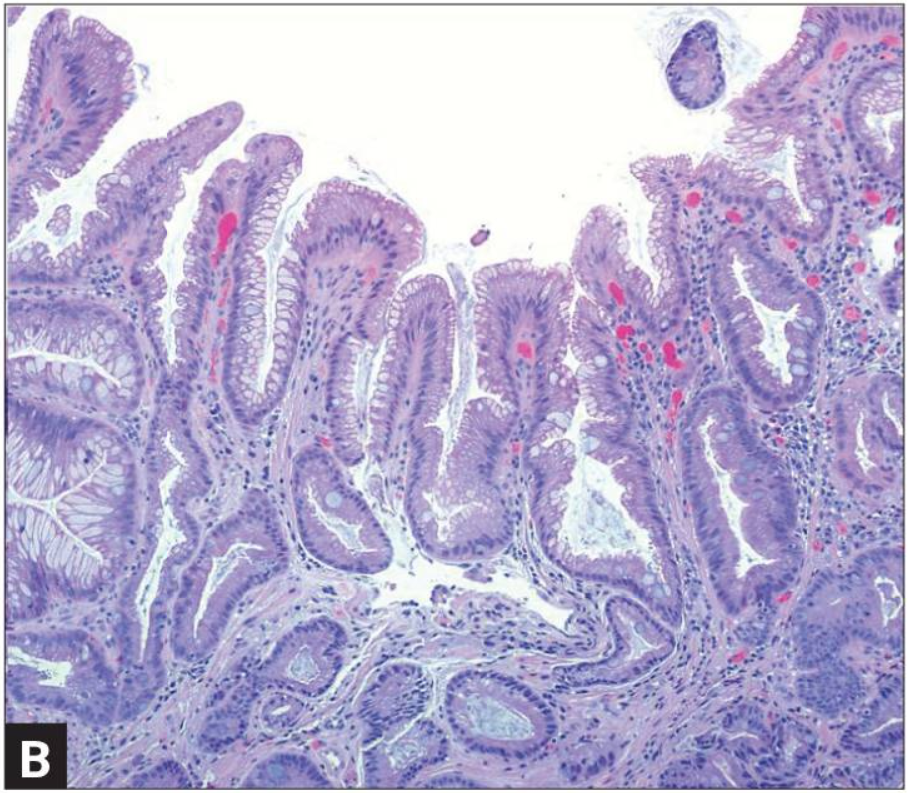

Кишечная метаплазия желудка определяется как замена поверхностного, фовеолярного, и/или железистого эпителия кислотопродуцирующей или антральной слизистой желудка кишечным эпителием. Кишечная метаплазия желудка характеризуется анатомически как ограниченный процесс, если он находится в одной области желудка или как обширный, если вовлечены две области желудка. Гистологически кишечная метаплазия желудка считается либо полной, либо неполной. Полный (I тип) кишечная метаплазия определяется слизистой оболочкой тонкой кишки со зрелыми абсорбирующими клетками, бокаловидными клетками (Гоблета) и щеточной каймой. Неполная (II тип) кишечная метаплазия секретирует сиаломуцины и сходна с толстокишечным эпителием с цилиндрическими “промежуточными” клетками на различных стадиях дифференцировки, неравномерными каплями муцина и отсутствием щеточной каймы.